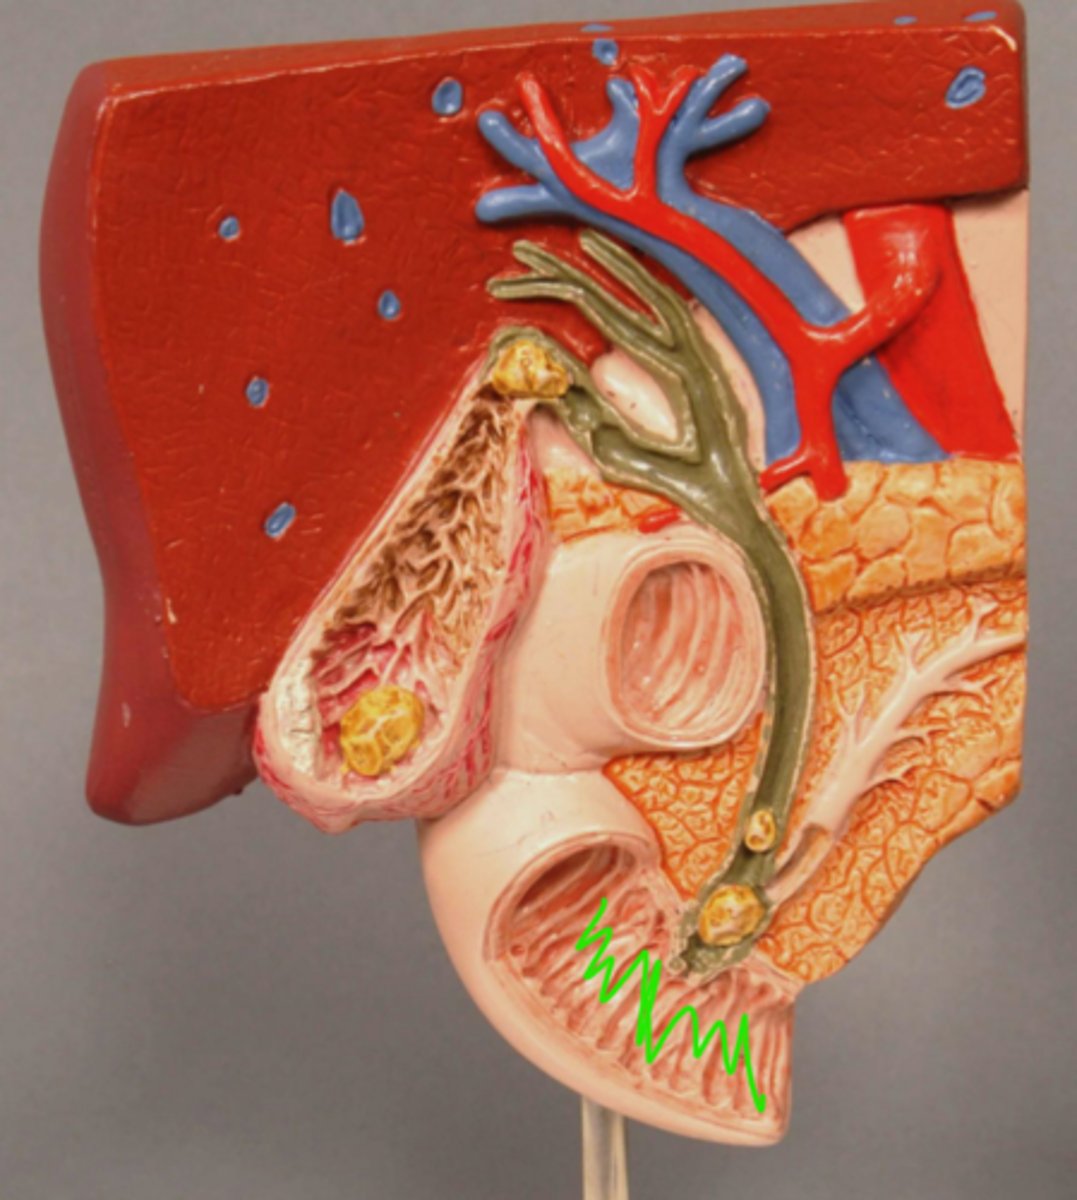

plicae circulares

Duodenum